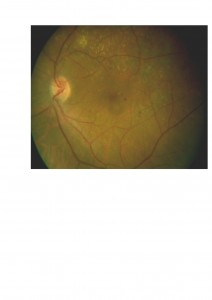

Desgraciadamente el tratamiento con láser consigue escasa o nula mejoría de la visión en otros tipos de edema macular diabético, tales como el edema macular difuso (cursa con ausencia o escasez de exudados lipídicos) y el edema macular asociado a anomalías de la interfase vítreo-macular del que ya hemos hablado en entregas anteriores.

Desgraciadamente el tratamiento con láser consigue escasa o nula mejoría de la visión en otros tipos de edema macular diabético, tales como el edema macular difuso (cursa con ausencia o escasez de exudados lipídicos) y el edema macular asociado a anomalías de la interfase vítreo-macular del que ya hemos hablado en entregas anteriores.